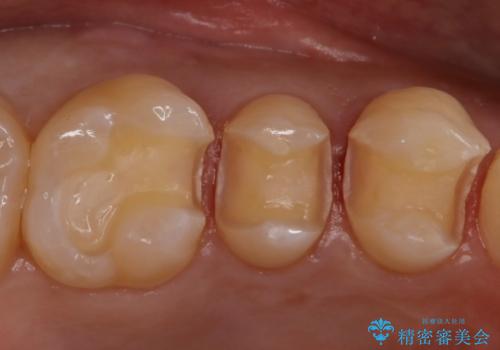

セラミックインレーのセット後は、食べ物がはさまることがなくなり、経過も良好で口腔内の環境もいい状態を保てています。